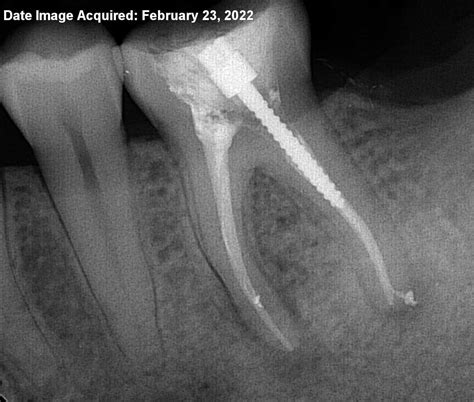

When you visit a dentist, they will perform a comprehensive examination to determine if the issue is indeed a canal root infection. This typically involves a visual inspection, testing the tooth for sensitivity, and using digital X-rays to visualize the extent of the decay and the health of the surrounding bone. These diagnostic tools are essential for mapping the root canals and identifying any hidden abscesses.

Root canal therapy is the standard procedure to treat a canal root infection. Contrary to popular myths, the procedure is designed to relieve pain, not cause it. The goal is to remove the infected pulp, disinfect the canals, and seal the space to prevent future reinfection.

3. Cleaning and Shaping: The infected pulp is carefully removed, and the root canals are meticulously cleaned and shaped with specialized instruments.

5. Filling: The cleaned canals are filled with a biocompatible material called gutta-percha.

6. Restoration: The access opening is sealed, and usually, a crown is placed over the tooth to restore its original strength and functionality.